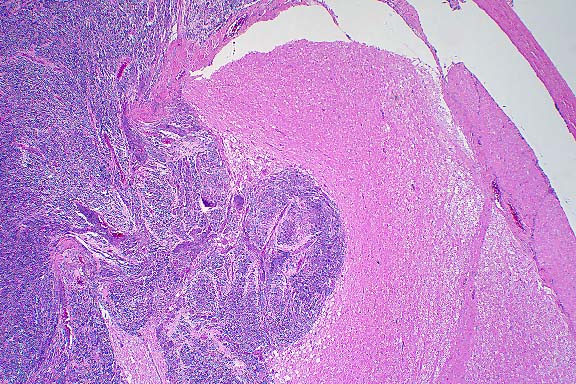

- Case 6-1. Spinal cord. This section (2x obj)

of spinal cord is expanded and replaced by an infiltrative mass

supported by a prominant fibrovascular stroma. Tumor cells are

quite pleomorphic, and characterized by oval to round cells which

may be closely associated or individualized, and include scattered

elongated cells separating the neuropil. Nuclei are hyperchromatic.

- Conference Note: The tumor histomorphology is consistent

with a primitive neuroectodermal tumor (PNET) and may represent

a primary tumor within the spinal cord, extension of a peripheral

PNET from spinal nerve roots into the spinal cord, or metastasis

from a primary brain tumor. The tumor is composed of a dense,

monomorphic population of small polygonal to spindled cells that

blend into the overlying meninges, separate and surround spinal

nerves, and compress and infiltrate the spinal cord parenchyma.

While infiltrative, the tumor is well delineated from the adjacent

preexisting neuropil. Neoplastic cells occasionally appear round

due to artifactual separation of the tumor and neuropil. Tumor

cells have indistinct cell borders with scant to small amounts

of eosinophilic cytoplasm and hyperchromatic nuclei that are

round to elongate and contain indistinct nucleoli. Occasionally,

neoplastic cells contain eccentrically placed nuclei that are

rounded on one end and taper at the opposite end with small amounts

of trailing eosinophilic cytoplasm ("carrot-shaped"

cells). There are rare rosettes.